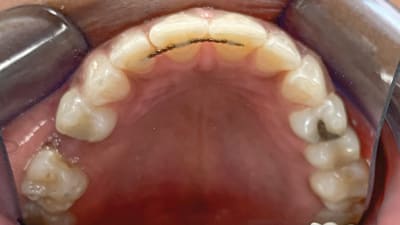

Products in Practice Orthodontics Making a Case for Adult Orthodontics With Clear Aligner Therapy Provided by the General Dentist By James P. Bennett, DDS October 01, 2022 11 min read